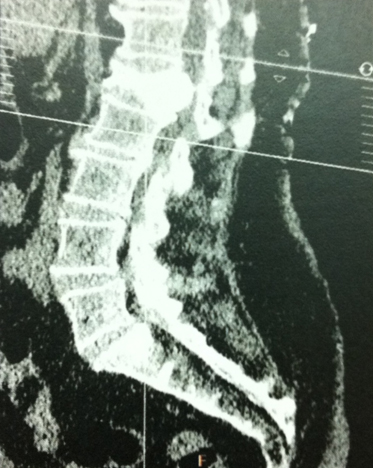

Mme S., 68 ans, a présenté une fracture vertébrale de L1. Le bilan biologique a conclu à une ostéoporose post-ménopausique.

Devant la persistance de douleurs dorsolombaires à 3 mois, malgré le traitement médical bien conduit, une cimentoplastie de L1 a été pratiquée.

Dans les suites, Mme S. a ressenti des paresthésies dans le territoire de L1 à droite. Une tomodensitométrie est pratiquée.